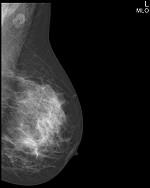

Шаг 3. Формат приемника рентгеновского изображения

В маммографии существует два общепринятых формата приемника рентгеновского изображения: 18х24 см и 24х30 см. На приемнике 18х24 см одномоментно (за одну экспозиции, без дополнительной укладки) можно исследовать грудь приблизительно до 2 размера включительно, а на приемнике 24х30 см - до 5 размера включительно.

Маммографы, рассчитанные на работу с приемников 18х24 см, стоят дешевле своих аналогов 24х30 см, однако маммографы с приемником 24х30 см являются более универсальными в своем применении.

Следует отметить, что исследование молочной железы большего размера, чем формат приемника, осуществляется в несколько экспозиций, что приводит к увеличению лучевой нагрузки на пациента, повышению общего времени обследования, повышению дискомфорта пациента, вызванного многократной компрессией органа, кроме этого, усложняется анализ серии рентгенограмм врачом рентгенологам.

Простой пример: во время скринингового обследования исследуют обе молочные железы в двух проекция (прямой и косой), если молочная железа целиком помещается на приемник, то делают четыре снимка, если молочную железу приходится снимать в два этапа, то делают уже 8 снимков.

◄ прямая проекция (кранио-каудальная) – CC (КК)

◄ косая проекция (медио-латеральная) – MLO (МЛК)